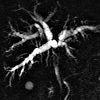

МРТ-холангиография